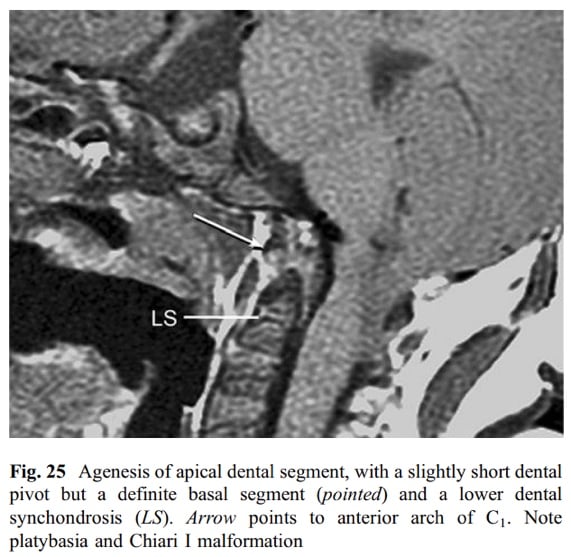

• Os Avis

• Rare anomaly

• the apical dental segment is attached to the basioccipital and is not fused to the main dental stem.

• The pivot is thus shortened but firmly fixed to the axis centrum, where a semi-lucent line representing the lower synchondrosis marks the successful integration of the two lower dens–axis components.

• Clinical features

• An os avis tends to be associated with neurological deterioration

• posterior dislocations of C1 on C2

• extremely unstable on extension: TAL is strapped against the os and therefore moves with the skull

• compressive symptoms